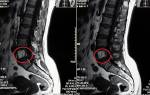

В некоторых особенно сложных случаях для точного диагноза может быть использована процедура МРТ.

Особенность асептического некроза заключается в том, что его проявления на рентгеновских снимках становятся заметными только через несколько месяцев после травмы, что является слишком поздним сроком для принятия необходимых мер.